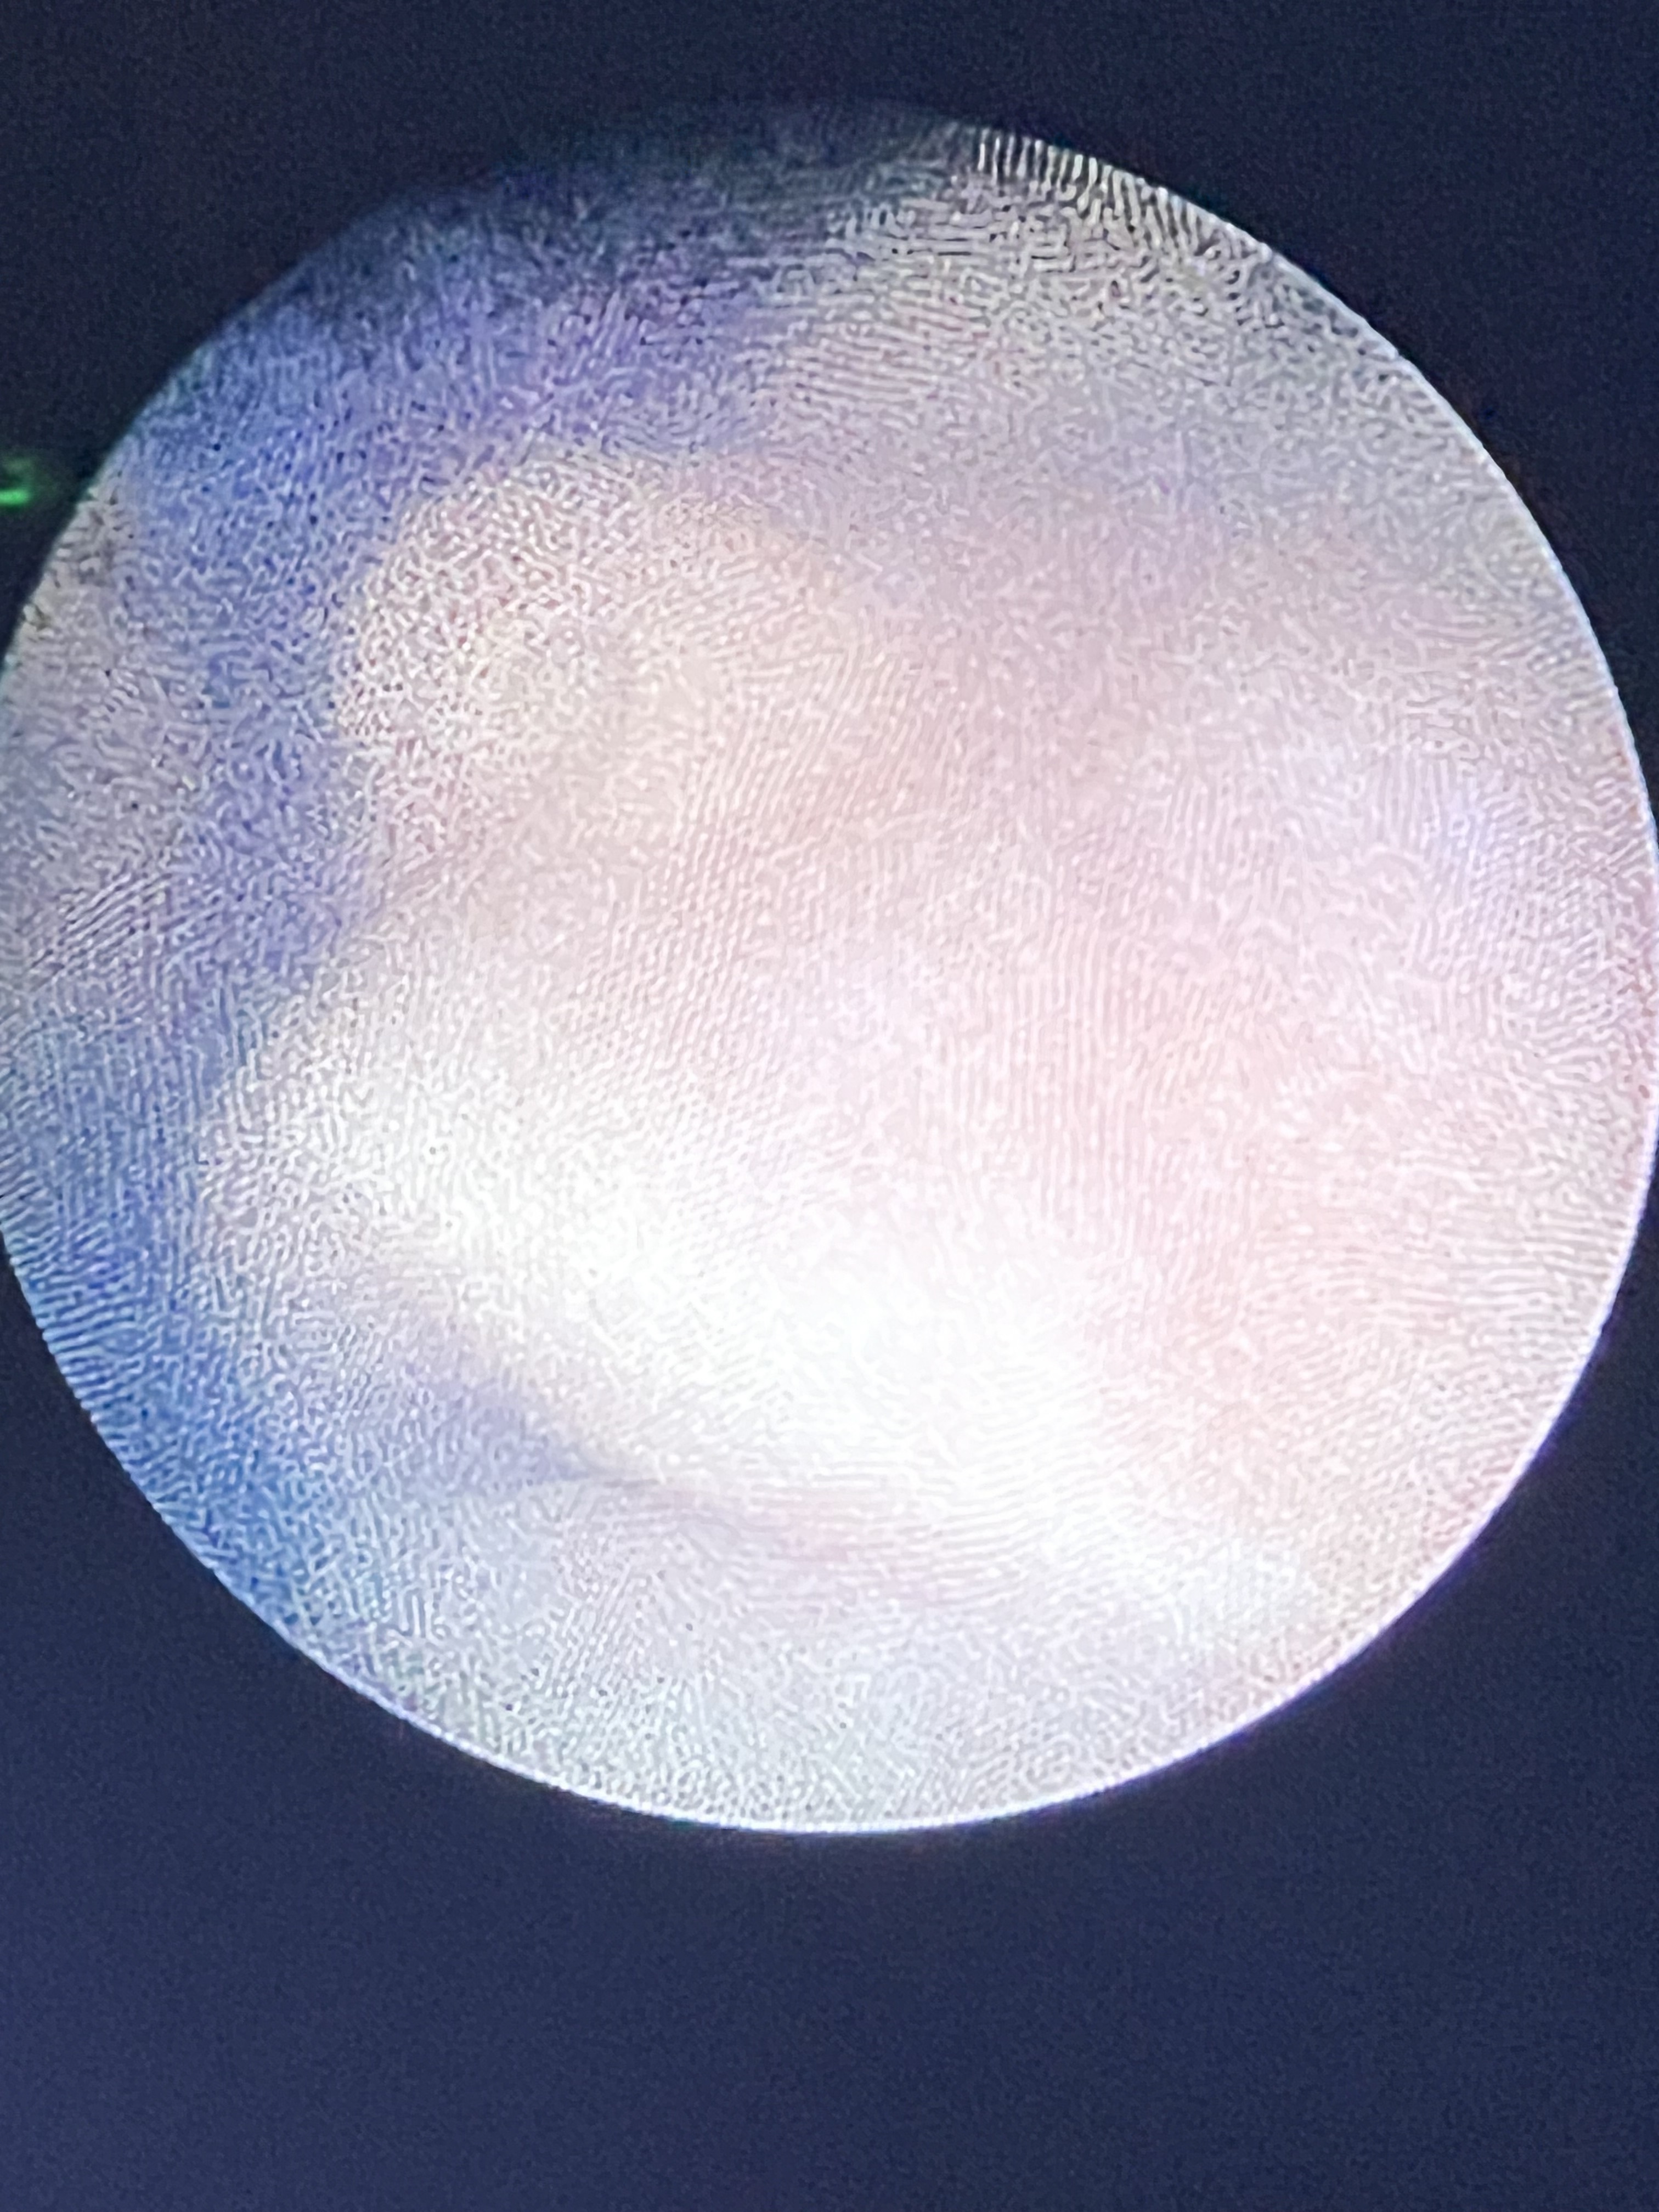

In this first case for the hospital, the mother presented with significant TTTS complications. The recipient fetus was experiencing heart failure and an accumulation of fluid in the abdominal and chest cavities. Banner’s fetal surgery team used a fetoscope inserted into the uterus through a small incision in the mother’s abdomen to close the twin fetus’ abnormal blood vessel connections and restored equal blood flow.

TTTS hand